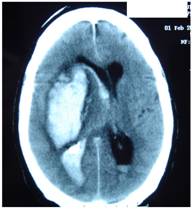

Figure 4 represents and example of ischemic stroke and hemorrhagic stroke on baseline and delayed CT with edema developing after 48 hours.

FIGURE 4

A. Ischemic stroke presenting with left hemiparesis. Normal CT on admission. CRP level: 6.9 m/dL; NT-PBNP level: 21pmol/L. B. CT scan after 48hours. Large infarction in the MCA territory showing mass-effect. CRP level: 7.9 mg/dL; NT-PBNP level: 139 pmol/L.